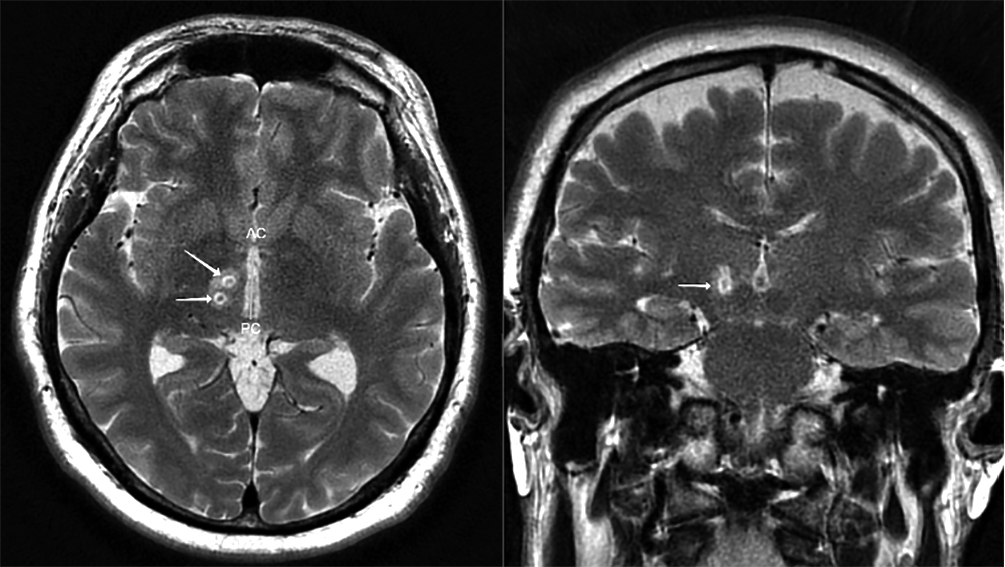

Оценка результатов лечения МР-ФУЗ в зависимости от мишени воздействия (рис. 2) показала, что достигнутое улучшение было более отчётливым при использовании PTT и комбинации мишеней VIM + PTT (p < 0,001, метод Крускала–Уоллиса). В группе пациентов с абляцией только VIM-ядра улучшение составило 32,0% (24,5; 40,2), при комбинированной абляции VIM и PTT — 50,0% (40,3; 57,5), а в группе с изолированной абляцией PTT — 40,1% (37,2; 58,7), различия статистически значимы (p < 0,001, метод Крускала–Уоллиса). Комбинацию мишеней проводили у пациентов в случае сохранения дрожания после формирования достаточного очага в проекции PTT. На рис. 3 представлена МРТ пациента с Д-БП после лечения посредством МР-ФУЗ с воздействием на PTT и VIM.

Рис. 3. МРТ пациента через 2 ч после одновременной абляции PTT + VIM справа (аксиальная и коронарная проекции).

Очаги абляции указаны стрелками.

Fig. 3. Patient’s MRI scan 2 h after simultaneous right-sided PTT + VIM ablation (axial and coronary planes).

Ablation lesions are shown with arrows.